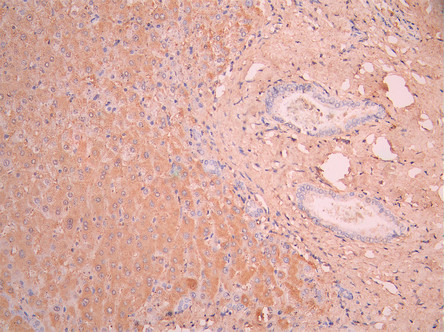

• IHC image of CSB-RA001939MA1HU diluted at 1:50 and staining in paraffin-embedded human liver tissue performed on a Leica BondTM system. After dewaxing and hydration, antigen retrieval was mediated by high pressure in a citrate buffer (pH 6.0). Section was blocked with 10% normal goat serum 30min at RT. Then primary antibody (1% BSA) was incubated at 4°C overnight. The primary is detected by a Anti-Human lgG, Fcy Fragment Specific labeled by HRP and visualized using 0.05% DAB.